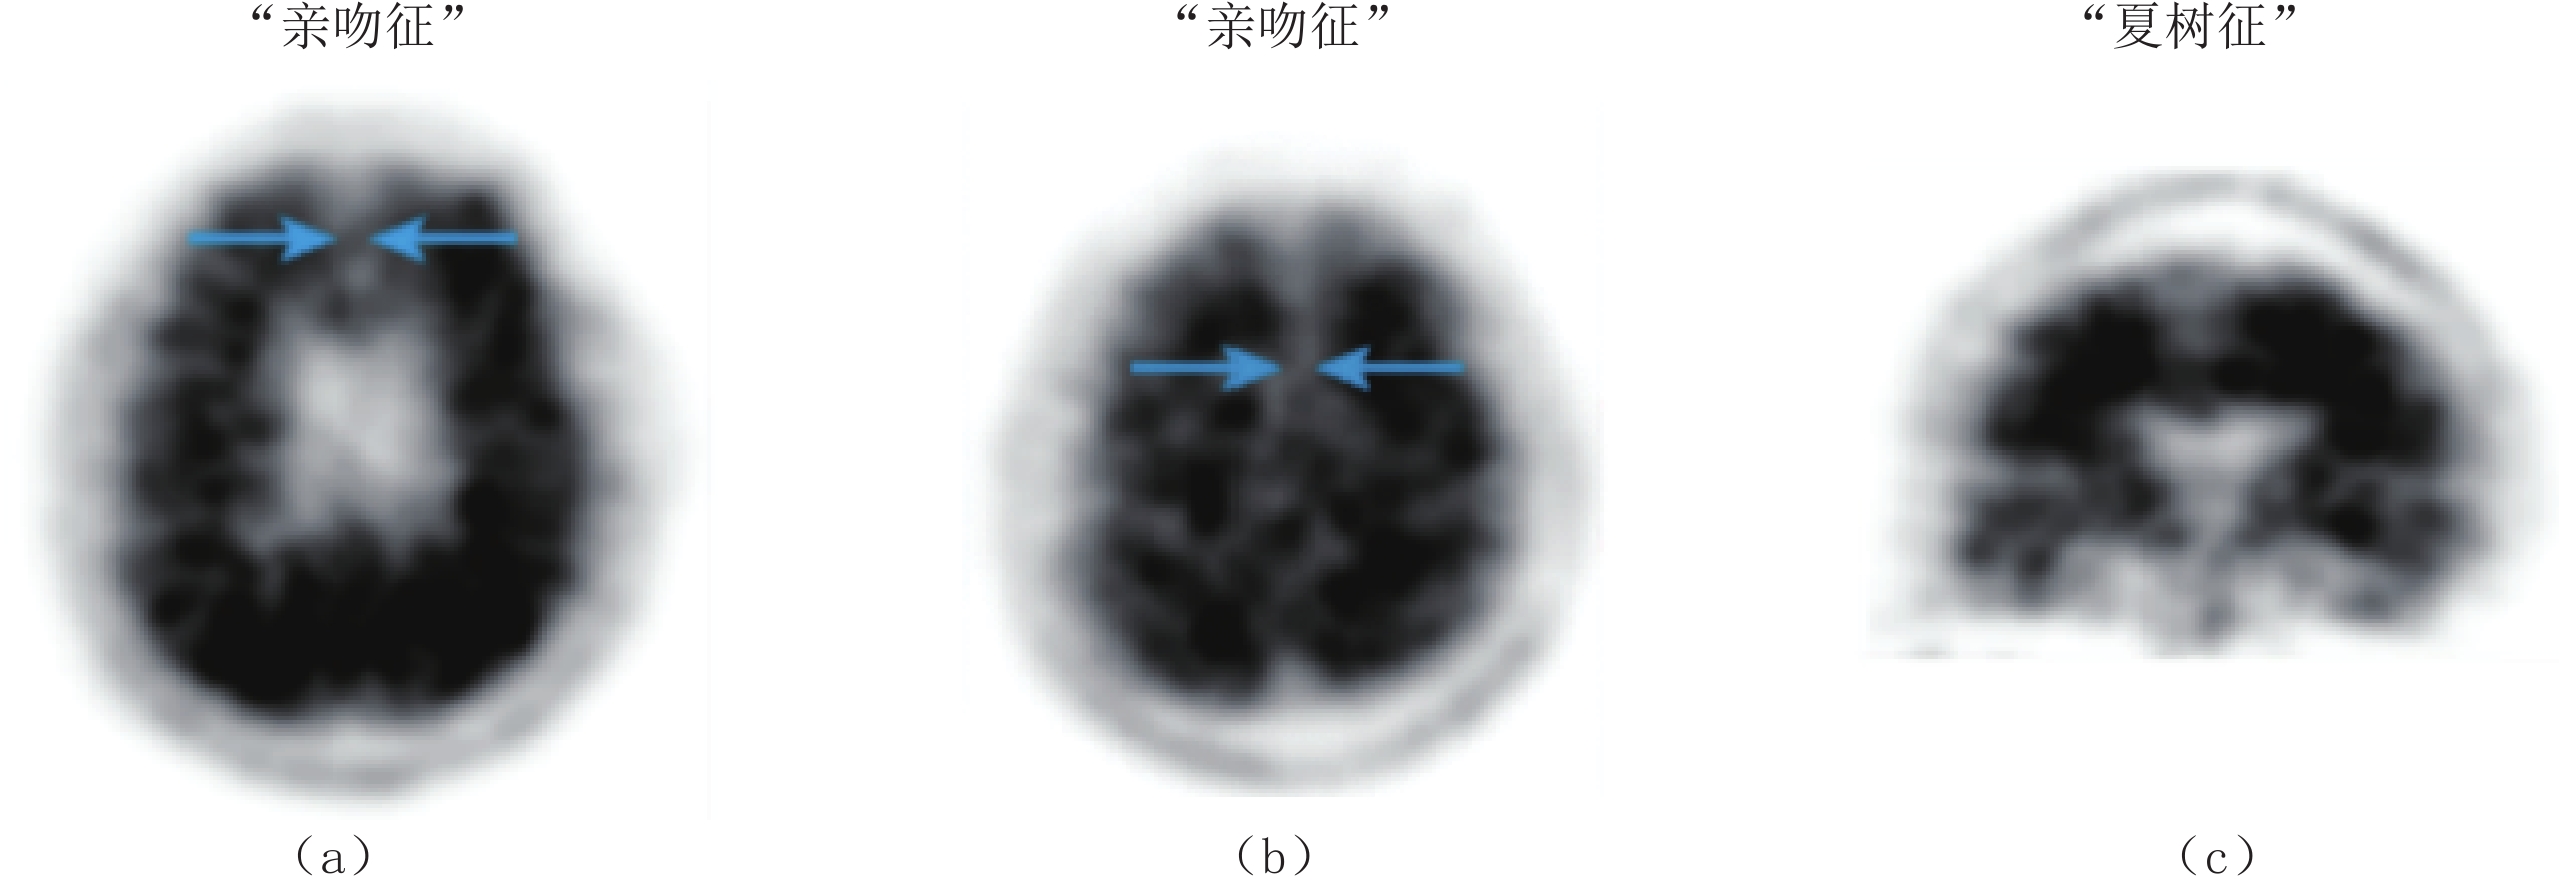

• 摘要: 基于多电压阈值方法的全数字正电子发射断层成像(PET)技术以“全数字”和“精确采样”为两个本质特点,实现软硬件解耦、系统“乐高”化搭建,打破了传统PET系统架构固定的限制,为更多创新应用的开展提供了可能。本文介绍了近年来应用专用型全数字PET系统的研究进展,阐述其在质子治疗监测、脑科学临床与基础研究、植物代谢研究等领域中的应用及其优势。面对前沿应用对PET成像系统提出的更高要求,进一步探讨全数字PET技术的发展趋势。

Abstract: Utilizing the Multi-Voltage Threshold method, All-Digital PET technology, characterized by "All-Digital" and "accurate sampling," facilitates hardware and software decoupling and modular "LEGO-like" system construction. This innovation addresses the limitations of traditional PET system architectures, enabling a broader range of innovative applications. This paper reviews recent advancements in application-specific All-Digital PET systems, highlighting their applications and advantages in proton therapy monitoring, clinical and basic brain science research, and plant metabolism studies. Furthermore, we explore the development trends of All-Digital PET technology to meet the increasing demands of PET imaging applications.